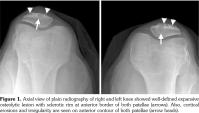

Laboratory tests including erythrocyte sedimentation rate, blood biochemistry, rheumatoid factor, anti-cyclic citrullinated peptide, liver function tests, and urinary analysis were normal except for uric acid value of 7.9 mg/dL (normal range 2.6-6.0 mg/dL) and C-reactive protein value of 2.1 mg/dL (normal range 0.01-0.82 mg/dL). Roentgenogram revealed lobulated, well-defined expansive osteolytic lesion with sclerotic rim at the anterior border of both patellae. The lesion in the right patella was 2x2.5 cm and the lesion in the left patella was 3x3 cm in diameter (Figure 1). Subsequent knee magnetic resonance imaging (MRI) showed bone marrow edema and well-defined expansive soft tissue lesions with low signal intensity on T1-weighted and high signal intensity on T2-weighted images (Figure 2a) in the anterior segments of the both patellae. Sagittal sequences demonstrated thickening and heterogeneous signal intensity in both patellar tendons (Figure 2b). The diagnosis of gouty involvement of the patella and patellar tendon was established according to the clinical, laboratory, and radiological findings. The patient was treated with colchicine 1 mg/day, and methylprednisolone 8 mg/day. Pain decreased in two weeks and he was able to resume his daily living activities more easily. Allopurinol 300 mg/day was started as urate-lowering therapy. Patient is under follow-up for five months and his serum uric acid level is 5.9 mg/dL.

Plain radiographic features of gout include soft tissue swelling and bony erosions. These features are generally normal in early gout.(4,12) MRI is critical for assessing abnormalities in bones, ligaments, and tendons within joints. MRI findings in these patients included bone marrow edema, tophi deposition of patella, and heterogeneous signal intensity in both patellar tendons. These findings are compatible with those of previous studies.(6,13) Such deposits present as masses with low signal intensity on T1 and intermediate to high signal intensity on T2-weighted images due to the presence of uric acid deposition and associated inflammation.(13,14) Differential diagnosis also includes chronic rheumatoid arthritis, pigmented villonodular synovitis, chronic infectious arthritis, and amyloidosis. The constellation of clinical and MRI findings often allow the specific diagnosis to be rendered.(15)